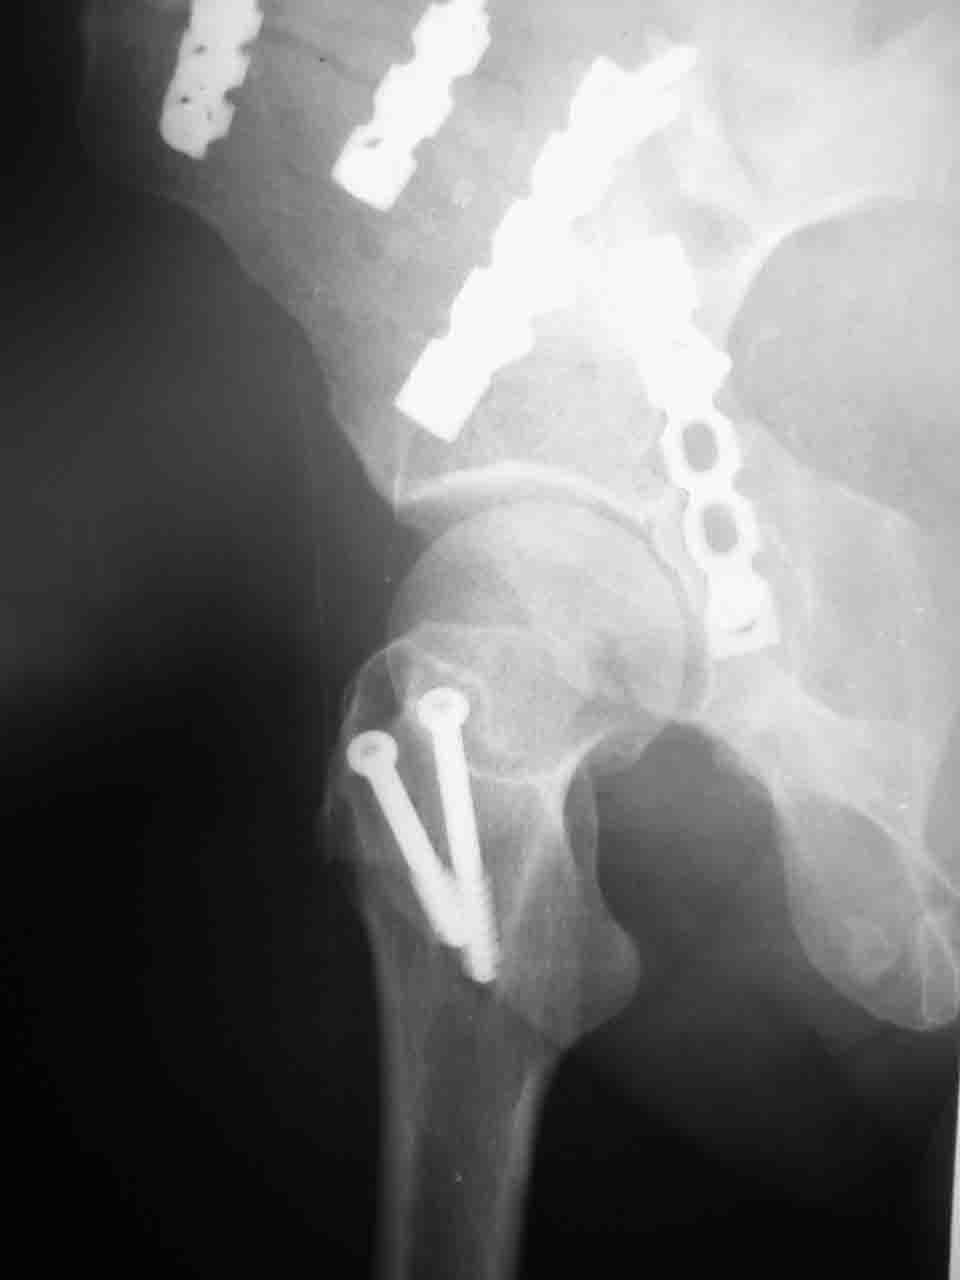

Уважаемые коллеги,43 летний мужчина, попав в автоаварию 13.10.2004, получил оскольчатый перелом обеих колонн левой вертлужной впадины.

На рентгенограммах - высокий двухколонный перелом вертлужной впадины с нарушением конгруэнтности, имеется обратная клиновидность суставной щели.

Спасибо за комментарии и рекомендации. Откровенно говоря, больного я прооперировал на прошлой неделе, через 5 дней после аварии и проблем с ним пока никаких нет, на удивление при достаточно обширной диссекции (илиофеморальный доступ) болей практически нет, так что больной самостоятельно садится в кровати, выполняет активные движения в оперированном суставе, сгибая до 60 градусов пока, далее с ассистенцией.

Причиной обращения к сообществу были возникшие непосредственно после операции сомнения и разочарования полученным качеством репозиции: а надо ли было трогать перелом вообще, репозиция передней колонны технически была очень сложна для меня, хотя реконструкции была в той же последовательности, что Д-р А.В.Рунков рекомендовал, в какой-то момент безуспешных манипуляций стал думать о *вторичной конгруэнтности*, которую не так давно обсуждали на

форуме и скелетном вытяжении. С репозицией и фиксацией задней колонны и отдельно задне-верхней стенки впадины проблем не возникло. Послеоп. Рг граммы в приложении. Если возникнут какие-либо дополнения или поправки - был бы признателен.